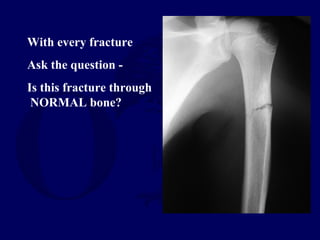

With every fracture

Ask the question -

Is this fracture through

NORMAL bone?

•Orthopaedic surgeon may be the first

to have opportunity to make the

diagnosis. (malignancy, metabolic

disease, etc.)